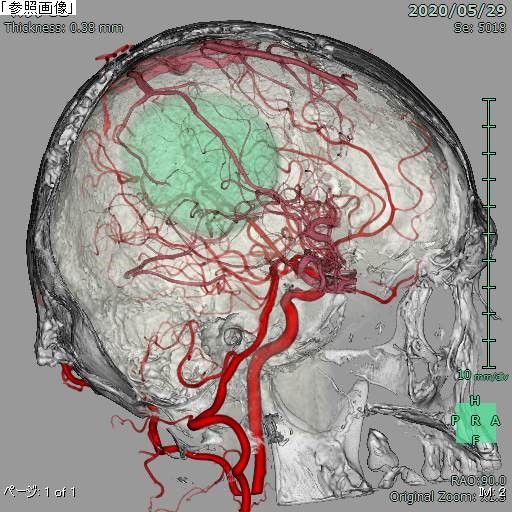

脳血管撮影

脳血管撮影では、頭頸部の血管をカテーテルから造影剤を流して撮影します。血管の走行を観察したり、必要に応じて血管の狭窄や閉塞を広げる治療や、動脈瘤をコイルで塞栓する治療、脳腫瘍などへの栄養血管に対して手術前の塞栓術を行ったりします。脳の血管をみる検査にはCTやMRIなどといった撮影もありますが、血管撮影装置での脳血管撮影ではそれらよりも細かい血管の状態まで観察することができます。

CT、MRIの画像と血管撮影での

造影画像を重ね合わせた3D画像(脳腫瘍)